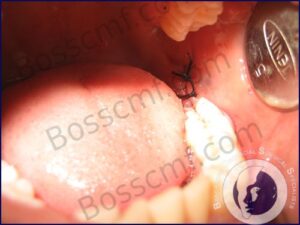

Wisdom teeth or third molars are the last teeth to erupt in the mouth. “inadequate space sometimes leads to partial or total lack of eruption resulting in “impacted” wisdom teeth. These teeth can cause several problems including local infection and damage to adjacent teeth and hence are removed, commonly by means of a small surgical procedure which usually involves drilling of surrounding bone.